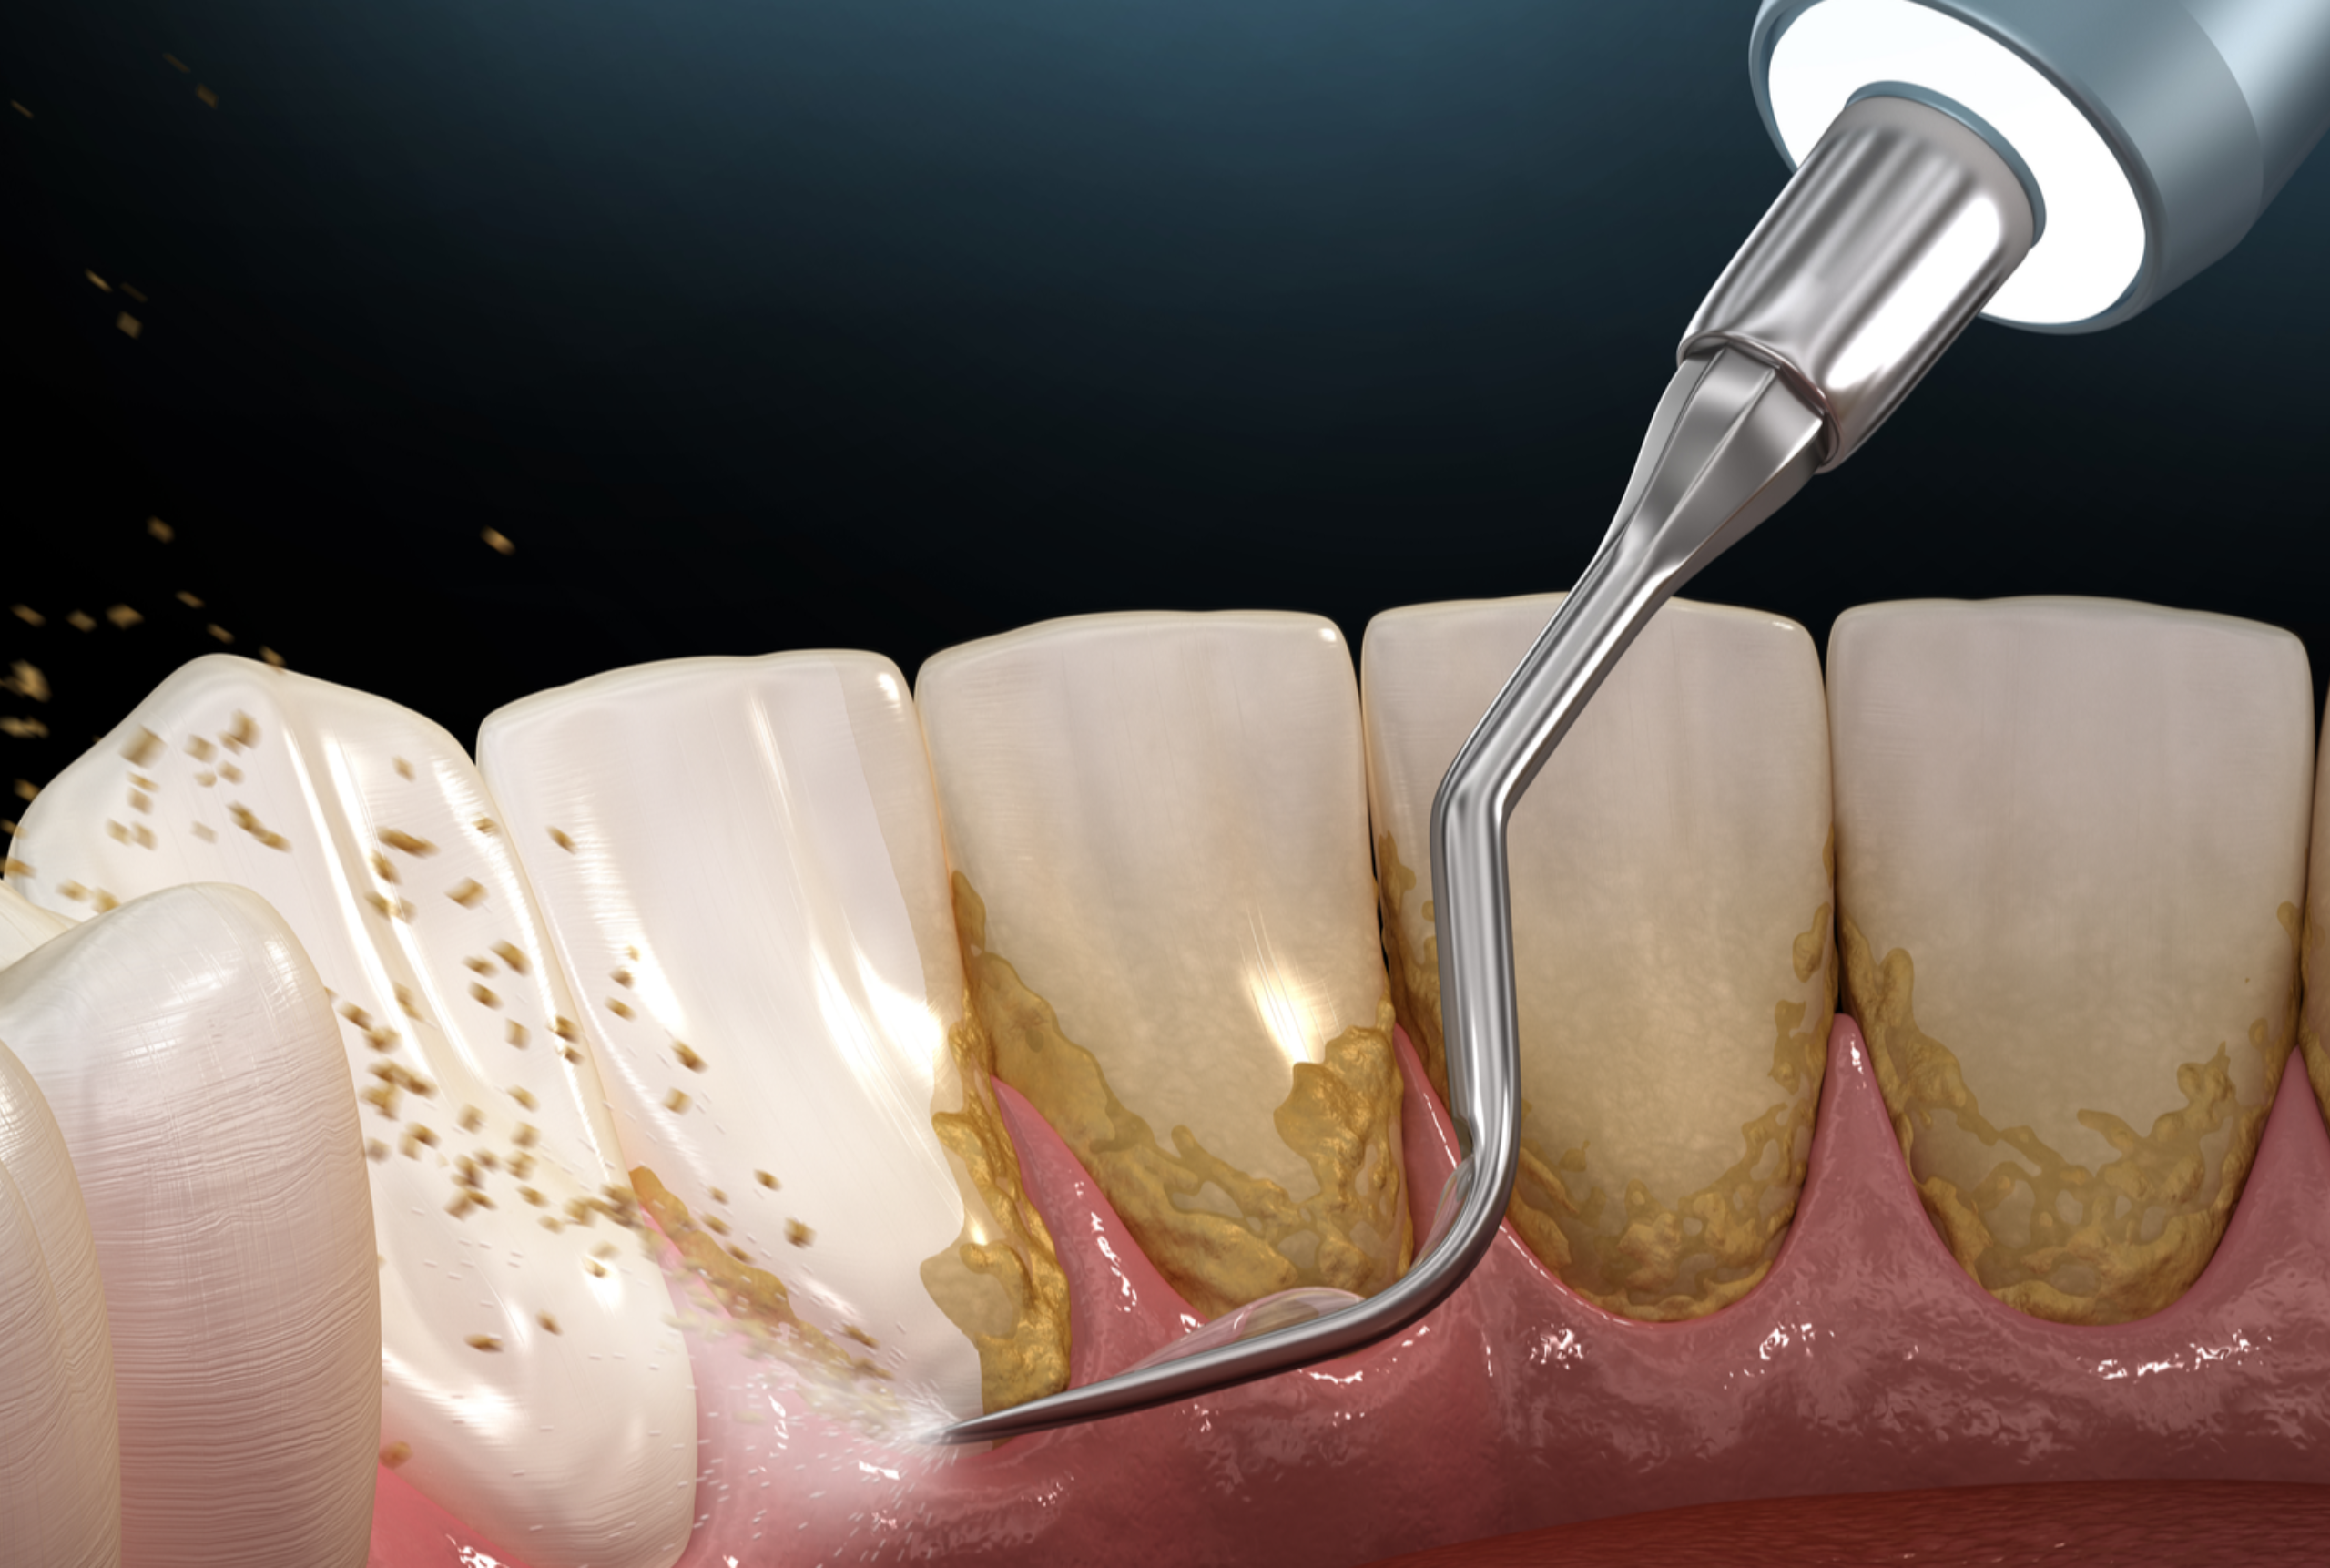

Scaling and gum surgery are specialized dental treatments designed to prevent, manage, and treat gum disease at different stages. While scaling helps remove plaque and tartar buildup that regular brushing cannot eliminate, gum surgery is recommended for advanced cases where infection has affected the deeper tissues and bone supporting the teeth.

Scaling is a professional deep-cleaning dental procedure used to remove plaque, tartar (calculus), and bacteria from the teeth surfaces and from below the gum line. These deposits cannot be removed by regular brushing or flossing. Scaling helps control gum infection, reduces inflammation, and prevents the progression of gum disease.

Plaque and tartar are carefully removed from the tooth surface and from below the gum line using advanced dental instruments. This helps eliminate bacteria and reduce gum inflammation.

The tooth roots are smoothed to prevent further plaque buildup and to help the gums reattach firmly to the teeth.